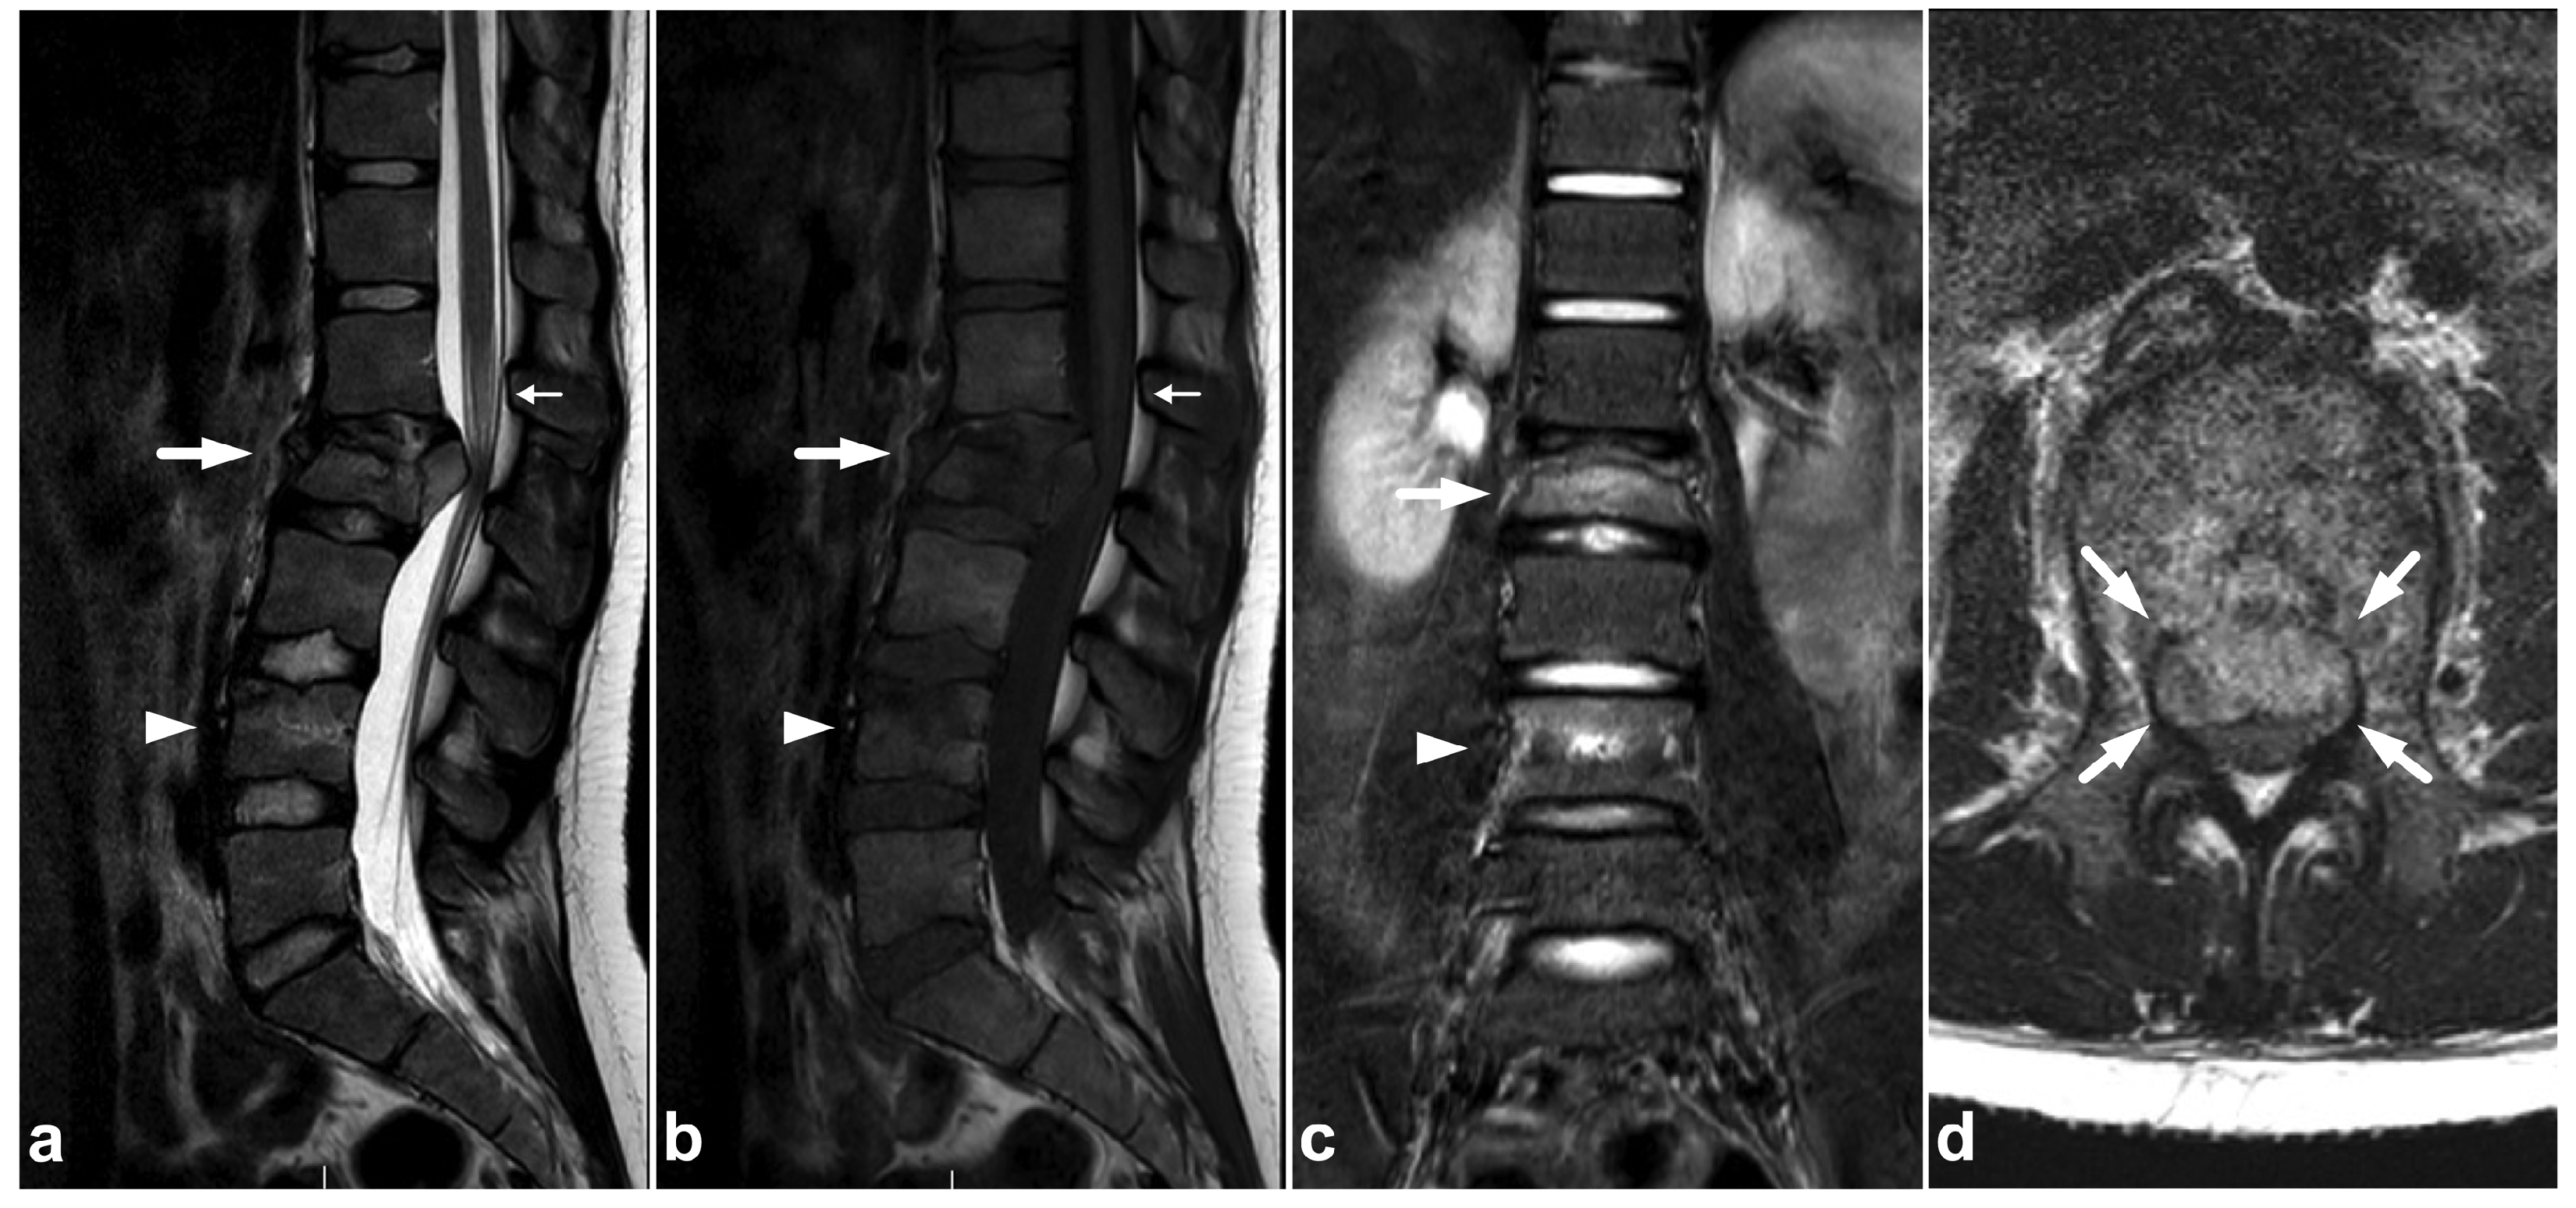

4.2. Posterior Ligament Complex

4.3. Anterior and Posterior Longitudinal Ligaments